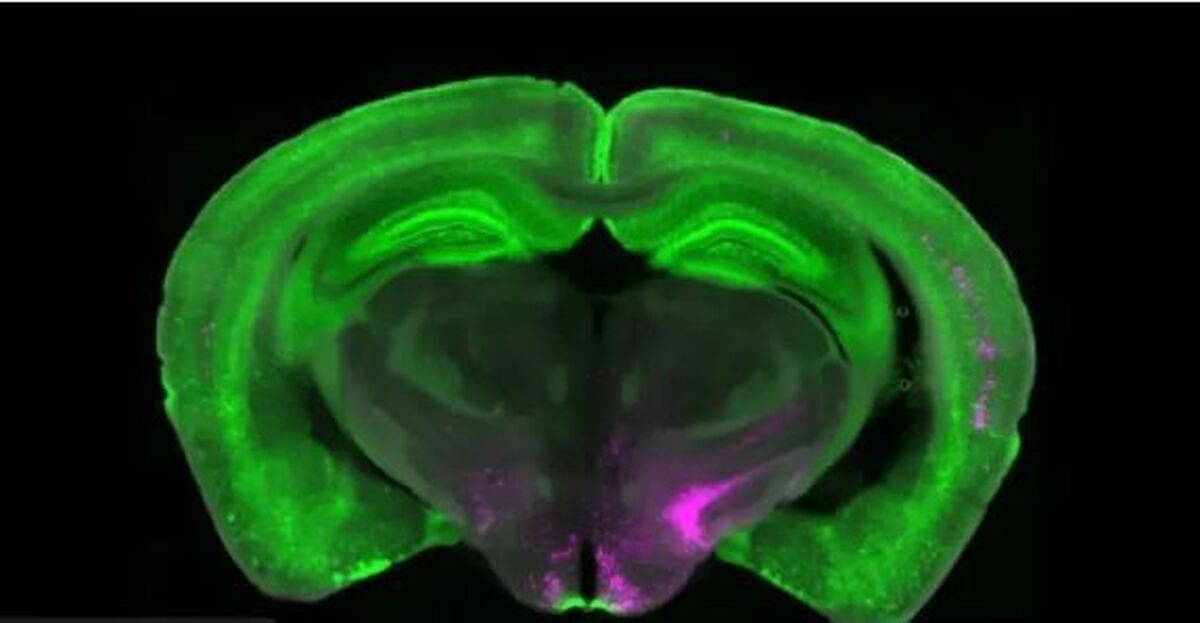

تیم تحقیقاتی بتلی با همکاری دانشگاه پیتسبورگ و موسسه پژوهشی اسکریپس گروهی از سلول‌های مغزی به نام نورون‌های گیرنده Y ۱ (Y ۱ R) را در ناحیه‌ای از ساقه مغز موسوم به هسته پارابرکیال جانبی شناسایی کردند.

پژوهشگران با استفاده از تصویربرداری کلسیمی فعالیت این نورون‌ها را در مدل‌های حیوانی بررسی کردند. نتایج نشان داد که این سلول‌ها در درد‌های طولانی‌مدت، فعالیت مداوم یا تونیک دارند؛ مشابه موتوری که پس از خاموش‌کردن خودرو همچنان روشن مانده باشد. این فعالیت پیوسته می‌تواند توضیح دهد چرا برخی افراد حتی پس از بهبودی کامل، همچنان درد احساس می‌کنند.

بررسی‌های دقیق‌تر نشان داد که نورون‌های Y ۱ R در یک ناحیه محدود از مغز متمرکز نیستند، بلکه به‌صورت پراکنده میان انواع مختلف سلول‌ها توزیع شده‌اند.

بتلی این وضعیت را چنین توضیح می‌دهد: انتظار داشتیم این نورون‌ها مثل خودرو‌های زرد در یک جای خاص پارک شده باشند، اما در واقع مثل رنگ زردی هستند که روی خودرو‌های قرمز، آبی و سبز پخش شده است. این پراکندگی شاید به مغز کمک کند تا انواع مختلف درد را در مدار‌های گوناگون کاهش دهد.